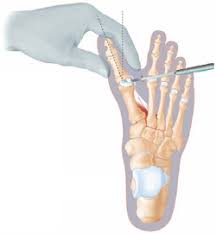

Die Chevron Osteotomie ist eine sehr effektive OP.

Während man beim Hallux valgus früher oft erst operiert hat wenn gar nichts mehr geht wird heute eher dafür plädiert zu operieren wenn der Schaden noch nicht zu komplexen Funktionsschäden im Bereich des Fußes geführt hat. Dabei muss es einen medizinischen Grund für die Operation geben. Zwei betroffene Frauen erzählen. Die Chevron Osteotomie ist eine sehr effektive OP. Die Ursachen liegen oft in der Kindheit. Im fortgeschrittenen Stadium ist nur noch ein operativer Eingriff möglich. Die Vielzahl von Behand. Meist schwillt diese Partie an. Ein Eingriff am Großzehenknochen meist eine Knochenumstellung Osteotomie begradigt die Zehe.